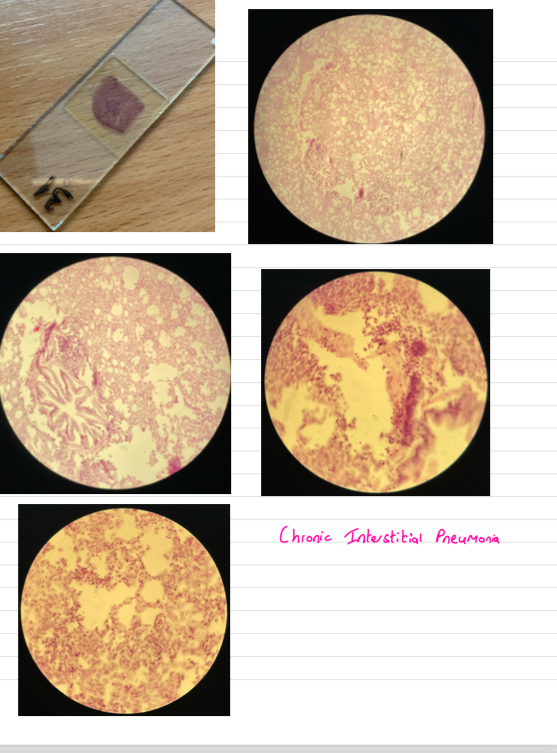

Chronic interstitial pneumonia

- thickened alveolar septa …narrowed lumen

- lymphoid follicles around bvs

- prolif of s.m cells